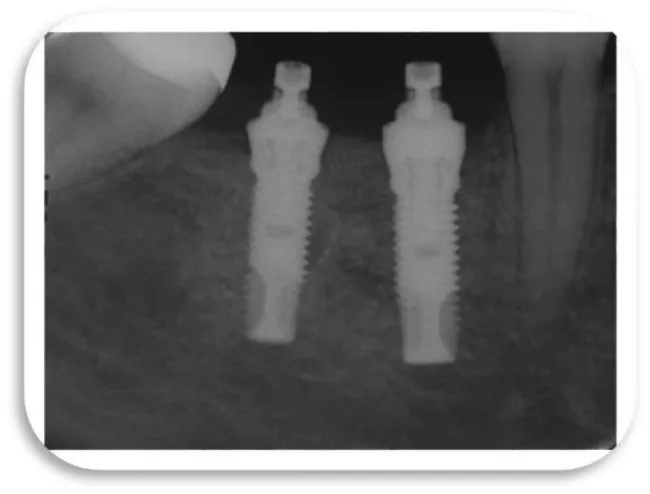

The eighth clinical case is a female 42 year old patient, which is in good health and with good oral hygiene habits. Before a 9-months, she received two titanium dental implants. The position of the placed dental implants were in the mandible, in the posterior right quadrant. The dental implants were placed due to the missing of the second premolar and the first mandibular molar. A control X-ray image was made to the patient because of the suspicion that she has a peri-implant disease. In the clinical examination, it was found that the gingiva around the dental implants was swollen and hyperemic. The impressions and minimal bleeding were observed on the gingival palpation. The bleeding from the gingiva occur during the process of probing, and pocket depth of 3.5 mm was detected. After the performed x-ray examination, a very small marginal bone resorption was detected аnd no surgical intervention was required (Figures 30-32).

Two dental titanium implants were placed in a 37 years old, male patient. These two dental titanium implants were placed one year ago and their position is 36, they compensate the lower left first molar. The patient come to dental office on control because he felt pain in the area of dental implants. The pain, except during mastication, was also manifested during the brushing of the teeth, and was accompanied by bleeding from the gums. Gingiva was hyperemic and oedematous (Figure 36), and X-ray control images were also made, which can be seen below (Figure 37-40). During the process of probing, the dental probe drowned in bone pocket around the dental implants at a depth of 10 mm.